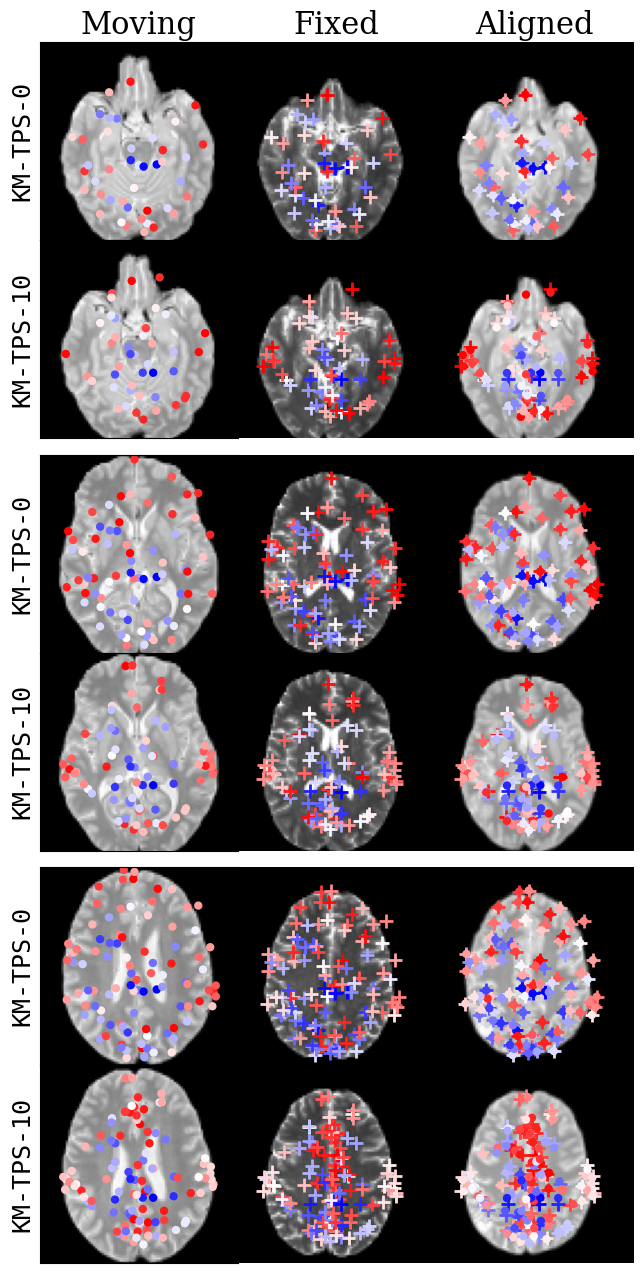

Refer to caption

Fig. 11: Keypoint visualization for a representative moving and fixed volume pair. For each slice, keypoints that are within 10 voxels of that slice are shown. Colors of keypoints reflect the distance of the keypoint to the visualized slice. For each slice, first row is KM-TPS-0, and second row is KM-TPS-10. Average distance between fixed (crosses) and aligned (dots) keypoints is 00 voxels for λ=0𝜆0\lambda=0 and 16.7916.7916.79 voxels for λ=10𝜆10\lambda=10.

In contrast to existing models that compute the transformation parameters using a “black-box” neural network, we can investigate the keypoints that KeyMorph learns to drive the alignment. Fig. 11 depicts the keypoints for a moving and fixed subject pair across three slices of the volume and for 2 model variants, KM-TPS-0 and KM-TPS-10. The “Aligned” slices show both warped (dots) and fixed (crosses) points. As expected, we observe that a TPS transformation with λ=0𝜆0\lambda=0 exactly aligns the moving and fixed points; this exact interpolation is relaxed for λ=10𝜆10\lambda=10.

Keypoint locations are trained end-to-end without explicit annotations. Therefore, we are interested in the effect of the transformation on the learned keypoint locations. We observe that the KM-TPS-0 keypoints are more evenly distributed over the volume, whereas KM-TPS-10 keypoints have a higher degree of regularity and clustering. We attribute this to the fact that at low values of λ𝜆\lambda, each keypoint is a separate degree of freedom and can locally influence the deformation, so spreading out the points maximizes utility. On the other hand, TPS with λ=10𝜆10\lambda=10 is “affine-like” and has a higher restriction on its local deformation; thus, the model learns to cluster the points in certain regions, which are largely subcortical; we conjecture that the variability across subjects is low in these regions.